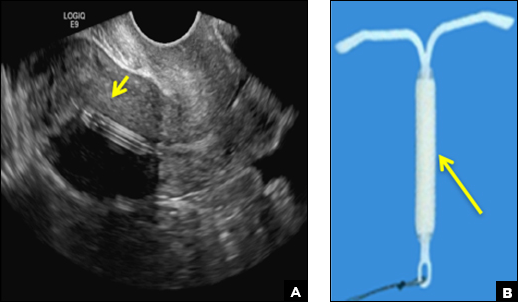

Mirena (Bayer) and Liletta (Allergan) are progestin-releasing intrauterine devices (IUDs) of similar size and shape. On ultrasonography, both the arms and the distal tip are echogenic. The progestin-containing plastic sleeve surrounding the stem in the middle demonstrates a laminated acoustic shadowing with distinctive parallel lines.1–4

(A) Transvaginal pelvic ultrasound demonstrates a well-positioned (fundally positioned) Mirena or Liletta levonorgestrel (LNG) IUD. Note the laminated appearance of the stem (short arrow). (B) Illustration of Mirena IUD with the plastic sleeve surrounding the stem (long arrow) corresponds to the laminated appearance on ultrasound.